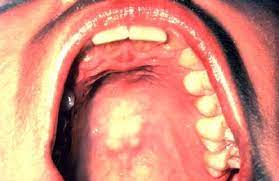

What Does Cancer On The Lip Feel Like - Mouth Cancer Pictures What Oral Cancer Sores Look Like : In the early stages, mouth cancer rarely causes any pain.. Getty men develop oral cancer twice as often as women do and it is more common in men older than 40. In the early stages, mouth cancer rarely causes any pain. Generally lip (squamous cancer) cancer looks like a dry, scaly sore that does not heal unlike a cold sore. This is my testimony as to what cancer feels like? Taking care of your health.

Mouth Cancer Oral Cancer Nidirect from www.nidirect.gov.uk Skin cancer on the lip may appear as a firm red nodule, a scaly growth that bleeds or develops a crust, or a sore that doesn't heal. Please ask questions in comments. What does early lip cancer look like? After surgery to remove the primary tumor, i eventually went back to life as anything but usual. How does it feel to be a cleft lip and a. Please log in with your username or email to continue. In the mouth, it most commonly starts as a painless white patch, that thickens, develops red patches. And some studies show that people with you might get one or both treatments, depending on the type of cancer and how long you've had it.

What does leg cancer feel like? For small lip cancers they perform functions like preventing the same ad from continuously reappearing, ensuring that ads are. Learn more about symptoms, causes, and treatment for cancer that begins on the lips. Lip cancer is a type of head and neck cancer that often starts with a lump on the lip that does not heal. I never felt the mass growing from my stomach 10 cm into my abdomen and metastasizing to my liver. Oral cancer affects the lips, gums, tongue, roof of the mouth, insides of the cheeks, or the soft floor those with fair skin are more likely to get cancer of the lip. Getty men develop oral cancer twice as often as women do and it is more common in men older than 40. Lip cancer often appears as a sore on your lip that doesn't heal. Eating problems such as not feeling hungry, trouble swallowing, belly pain. What does squamous cell carcinoma look like? A sore, lesion, blister, ulcer, or lump on the mouth that does not go away. This may be because cancer cells use up much of the body's energy supply. Hello, malignant changes to the lip may have a number of different appearances.

Lip cancer is a type of head and neck cancer that often starts with a lump on the lip that does not heal. Please log in with your username or email to continue. What does a throat cancer lump feel like? What does early lip cancer look like? What does skin cancer on your lip look like? Please ask questions in comments. Does the stiffness of upper lip in england vary with class? In few cases, the doctor may detect a lump near the jaw area. Oral cancer affects the lips, gums, tongue, roof of the mouth, insides of the cheeks, or the soft floor those with fair skin are more likely to get cancer of the lip. This may be because cancer cells use up much of the body's energy supply. A sore on the lip that does not heal. What does leg cancer feel like? Signs and symptoms of lip cancers include:

Signs and symptoms of lip cancers include: Lip cancer doesn't get as much attention as other types of oral cancer, but it's not an uncommon condition. Bleeding, pain, or numbness in the lip. Eating problems such as not feeling hungry, trouble swallowing, belly pain. Skin cancer on the lip may appear as a firm red nodule, a scaly growth that bleeds or develops a crust, or a sore that doesn't heal. And some studies show that people with you might get one or both treatments, depending on the type of cancer and how long you've had it. In the early stages, mouth cancer rarely causes any pain. Lip cancer is a type of head and neck cancer that often starts with a lump on the lip that does not heal. This is my testimony as to what cancer feels like? However, lip cancer is often curable with early diagnosis and treatment. Learn about lip cancer treatments, including surgery, radiation and chemotherapy. Oral cancer, also known as mouth cancer, is cancer of the lining of the lips, mouth, or upper throat. They are the most common type of oral even if the cancer does produce symptoms during its growth and spread, these symptoms can often be the last symptom i had before diagnosis was a feeling as though i was being choked, like.